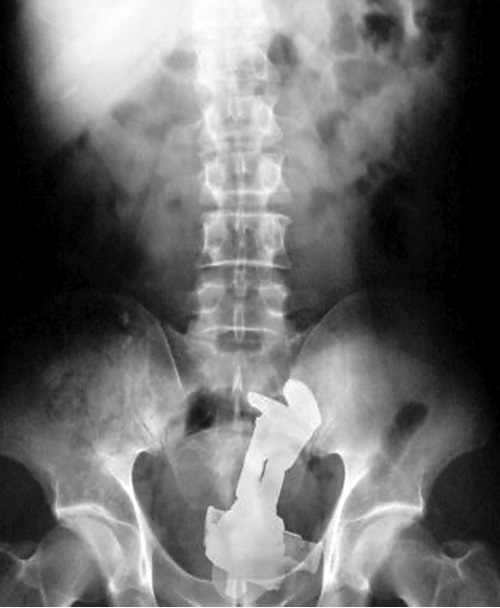

Malum Bölgelerine Kazayla Giren Nesneler Sonucu Acile Kaldırılmış İnsanların 15 Röntgen Görüntüsü Bu nesnelerin orada olmasının mantıklı hiçbir alakası yok. Büyük ihtimalle bir kaza sonucu bu durum oluşmuştur. Aksini düşünmek bile istemiyorum. Foto Galerimizin devamını görmek için Lütfen sonraki sayfaya geçiniz..